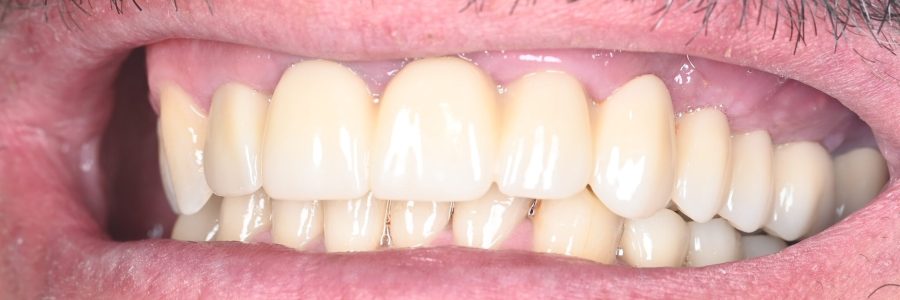

Redarea funcției masticatorii și estetice prin restaurări complexe cu ajutorul coroanelor pe implanturi tip FP1, cu aspect natural si sănătos al gingiei.

Lucrarea finală este realizată individual, în funcție de forma feței și de zâmbet, cu materiale biocompatibile și aspect natural.

Dantura fixă arată natural?

Da. Lucrarea finală este realizată personalizat pentru fiecare pacient, cu materiale ceramice sau compozite care reproduc perfect aspectul natural al dinților.